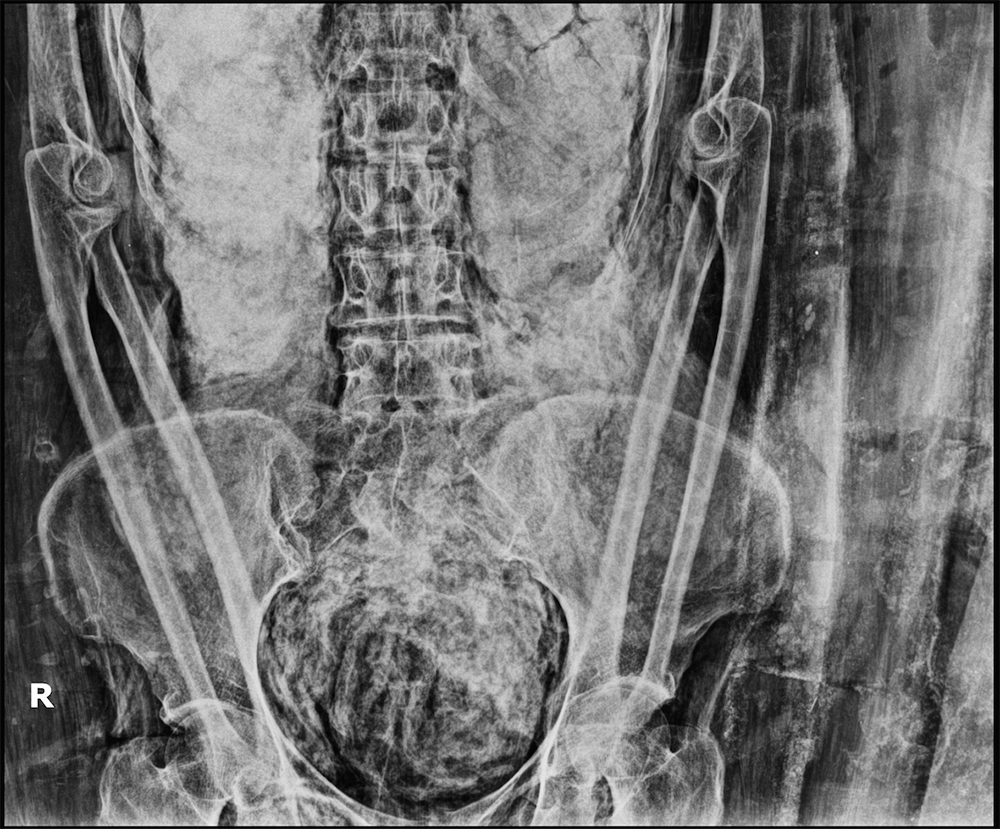

Early on, CT may be positive when the CXR is negative. The typical GGO distribution is similar, but usually more extensive than on CXR (Fig. 3).